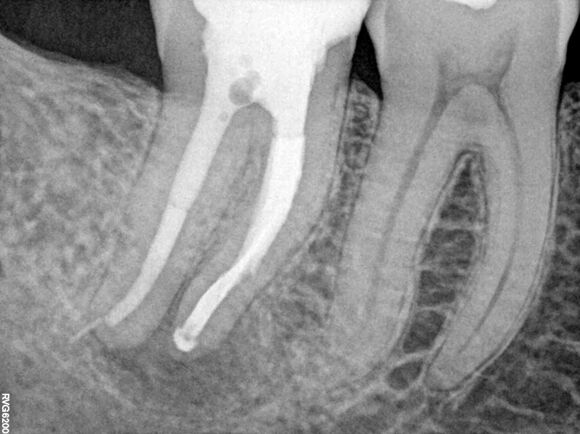

Beispiel 3: Vorher

Unvollständige Wurzelfüllung mit anhaltenden Beschwerden.

Beispiel 3: Nachher

Verlängert, vervollständigt und Beschwerdefreiheit.